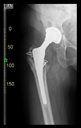

The direction of the cup stem was determined by the guide wire. The aiming device was needed to introduce this wire. After removing the aiming device, the next step was the drilling. Since a cannulated drill bit was used, the previously installed wire could guide the process. A self-positioning reaming tool was then used in the drilled channel. In the prepared cavity, the cup was fitted perfectly. Of the two stemmed cups available to us, the McMinn cup (Waldemar Link, Hamburg, Germany) had the simpler geometry and was therefore chosen. The stemmed cup was inserted according to the manufacturer’s recommendation. In the presence of a significant bone defect, a synthetic bone graft may be impacted for substitution.

The radiological examination allowed us to verify the close bone-to-implant contact and the unchanged position of the implant during follow-up.

In all the cases operated with the above-described targeting procedure, the stems of the cups remained between the cortical bone surfaces without perforation of the linea terminalis, as shown by postoperative radiographs. There were no complicated surgical situations. In 16 cases, the wound healings were uneventful, and the hips were able to bear weight again after postoperative rehabilitation.